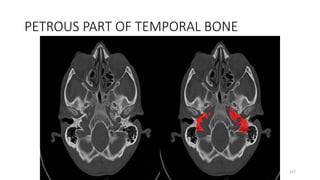

PETROUS PART OF TEMPORAL BONE

lacrimal, frontal

PETROUS TEMPORAL

• Emissary vein

• Sigmoid sinus

Foramen magnum

MAGNUM MAGNA